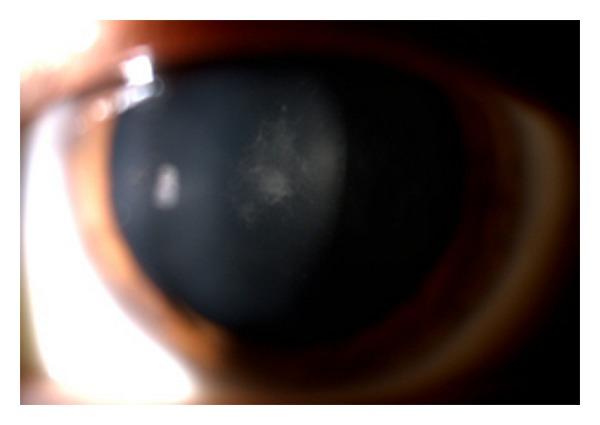

We present a case of retinitis pigmentosa (RP) related cystoid macular edema (CME) refractory to oral acetazolamide and topical ketorolac that was treated with intravitreal and subtenon depot triamcinolone. A 32-year-old male with RP presented with complaints of bilateral decrease in visual acuity. His best-corrected visual acuity (BCVA) was 20/50 in the right eye and 20/100 in the left eye. After being informed of the available treatment options, the patient received bilateral intravitreal injection triamcinolone. The patient's BCVA improved to 20/40 in the right eye and 20/50 in the left eye and the CME was resorbed. However, 5 months after the injection in the left eye and two months in the right eye, visual acuity decreased due to recurrence of CME. We performed a second intravitreal injection in the left eye with improvement of visual and anatomic results, but we observed a recurrence of CME. Afterwards, we treated the patient with subtenon depot triamcinolone in both eyes, with the result that there was no recurrence after 4 months in OD or after 3 months in OS. We conclude that intravitreal and subtenon depot triamcinolone appear to provide at least temporary benefit in refractory CME as regards the improvement of visual acuity.

我们报告一例视网膜色素变性(RP)相关的黄斑囊样水肿(CME),该患者对口服乙酰唑胺和局部应用酮咯酸治疗无效,随后接受了玻璃体内及Tenon囊下注射曲安奈德治疗。一名32岁患有RP的男性患者,主诉双眼视力下降。他的最佳矫正视力(BCVA)右眼为20/50,左眼为20/100。在被告知可用的治疗方案后,该患者接受了双眼玻璃体内注射曲安奈德。患者的BCVA右眼提高到20/40,左眼提高到20/50,且CME消退。然而,左眼注射后5个月,右眼注射后2个月,由于CME复发,视力下降。我们对左眼进行了第二次玻璃体内注射,视力和解剖学结果均有改善,但我们观察到CME再次复发。之后,我们对患者双眼进行Tenon囊下注射曲安奈德,结果右眼4个月后、左眼3个月后均未复发。我们得出结论,就视力改善而言,玻璃体内及Tenon囊下注射曲安奈德似乎至少能为难治性CME提供暂时的益处。